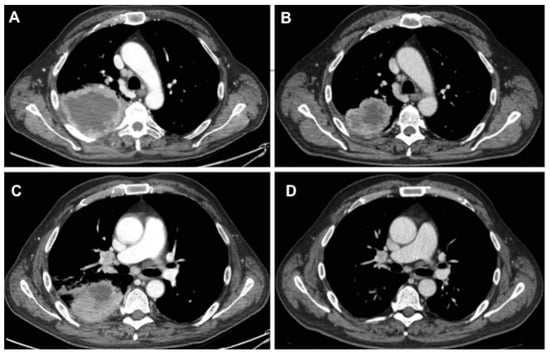

All patients evaluated in this study received previously a cytological or histological diagnosis of NSCLC and standard staging procedures and they were judged to be unresectable at the time of presentation, on the basis of (a) an extended mediastinal lymph node involvement or (b) the presence of locally advanced disease or (c) a distant metastatic disease (oligometastatic). Thus, they received TKIs or ICIs therapy as a definitive treatment as the first or second line treatment; they were referred for surgical intervention if the computed tomography (CT) scan or positron emission tomography (PET) scan findings were suggestive of a response to the disease in terms of a reduction of mediastinal lymphadenopathy and/or the primary tumor (Figure 1), or good control of distant metastatic disease (i.e., brain metastasis treated by radiation therapy).

Figure 1. Computed tomography scan showing the initial radiological aspect of tumor and lymph nodes (A,C) compared to the aspect after treatment with pembrolizumab (B,D).